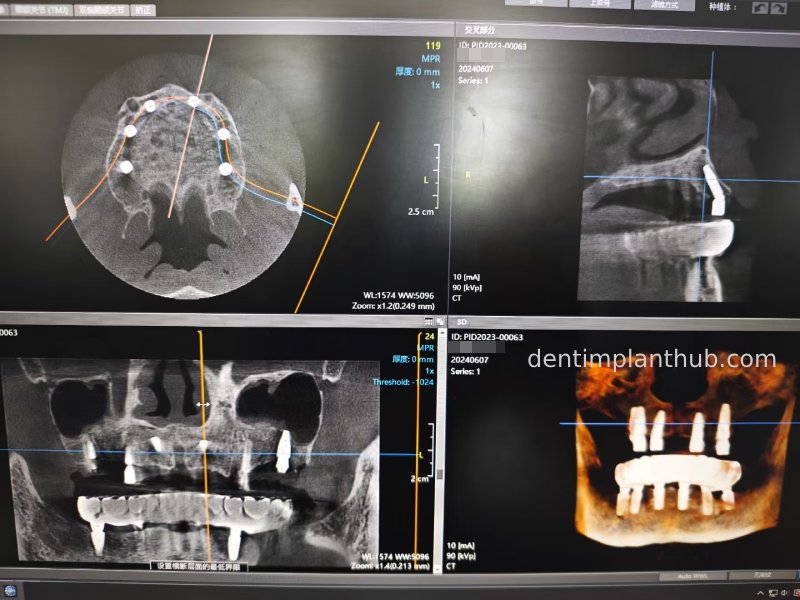

CBCT review results on 13 May '24

46

44

42

32

34

36

Maxillary condition as shown by CBCT on 13/5/24

16

14

12

22

24

26